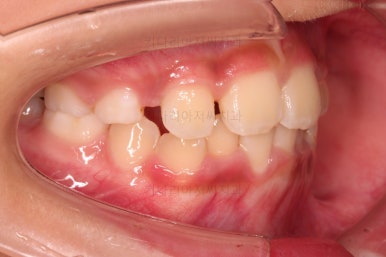

1. 초진

초진 시 입안의 모습입니다.

가장 눈에 띄는 건, 아랫니가 윗니보다 앞에 나와있는 부정교합인데요.

치료 한 달 째 사진인데요.

벌써 반대교합이 많이 좋아지고 있습니다.

턱의 위치도 좋아지고, 많이 :삐뚤었던 앞니도 일정 부분 위치가 좋아지고 있습니다.